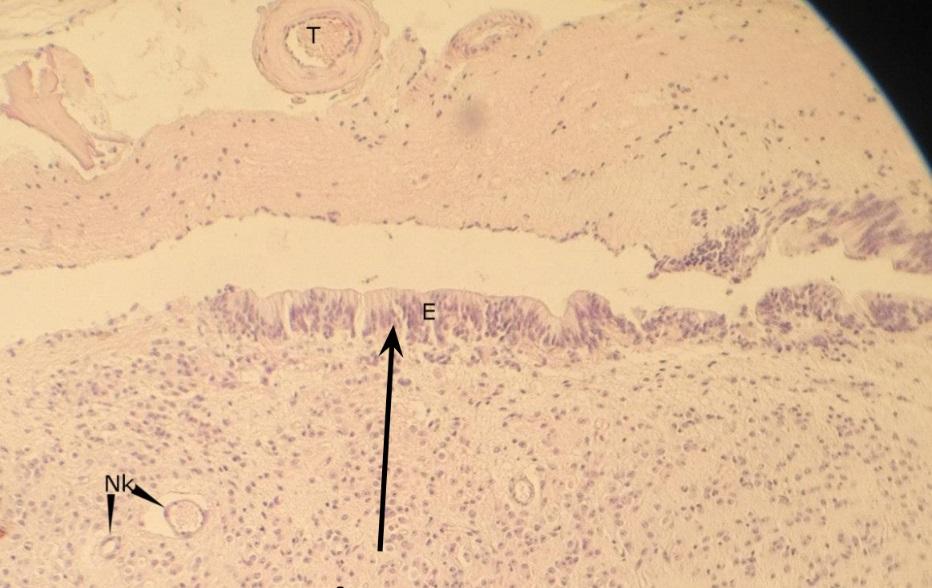

Pytanie 262

zachyłek komory trzeciej (szyszynka)

Pytanie 263

nabłonek ependymalny - ependymocyty (szyszynka)

Pytanie 264

naczynie krwionośne (szyszynka)

Pytanie 265

pinealocyty (szyszynka)

Pytanie 266

opona miękka (szyszynka)

Pytanie 267

pola glejowe - jasne ciapki z komórkami śródmiąższowymi glejowymi (szyszynka)

Pytanie 268

pinealocyty - skupiska (szyszynka)